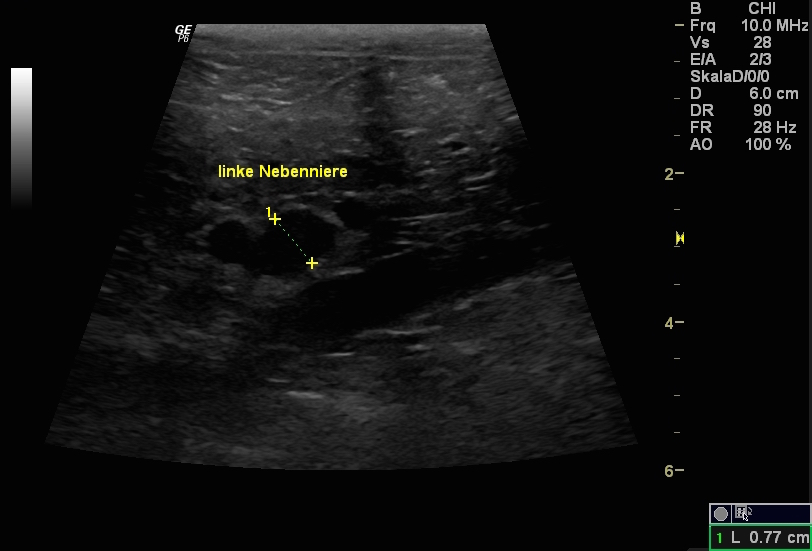

Im Rahmen einer Ultraschall-Untersuchung der Bauchorgane fiel eine stark vergrößerte Leber auf. Die Nebennieren wiesen grenzwertig große Durchmesser auf (Abb. 2, Abb. 3).